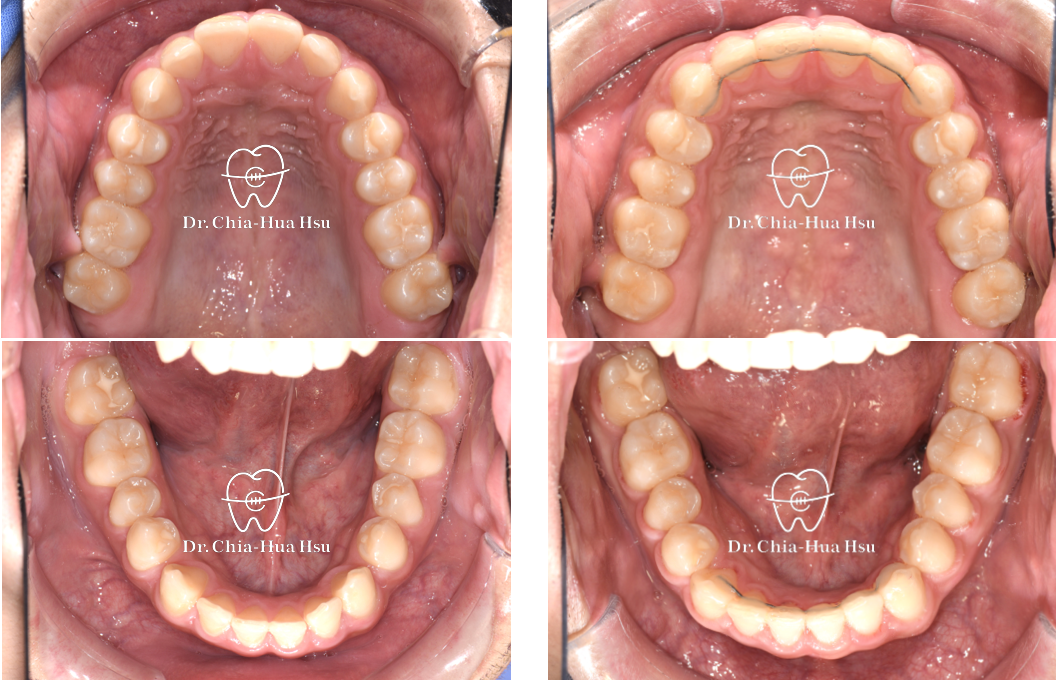

治療前

治療後

上顎擴弓:青少年使用骨釘輔助上顎擴弓器,將過窄的上顎牙弓撐寬。

治療中